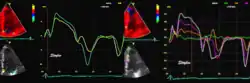

Colour tissue Doppler

Unlike spectral Doppler, colour tissue Doppler samples velocities from all points of the sector, by shooting two pulses successively, and calculating the velocity from the phase shift between them by autocorrelation. The calculation is slightly different from the true Doppler effect, but the result becomes identical. This results in a single velocity value per sample volume. The result is a velocity field of (nearly) simultaneous velocity vectors towards the probe. The advantage of colour Doppler over spectral Doppler is that all velocities can be sampled simultaneously. The disadvantage is that if there is clutter noise (stationary reverberations), the stationary echoes will be integrated in the velocity calculation, resulting in an under estimate. As pulsed wave Doppler are displayed as a spectrum, the colour Doppler values will correspond to the mean of the spectrum (in the absence of clutter), giving slightly lower values. In the HUNT study, the difference in peak systolic values were about 1.5 cm/s.[26]

The local velocities are not the result of the local function, as segments are moved by the action of neighbouring segments. Thus the velocity differences velocity gradient are the main measure of regional contraction, and has become the most important employment of colour tissue Doppler, in the method of strain rate imaging.[27]